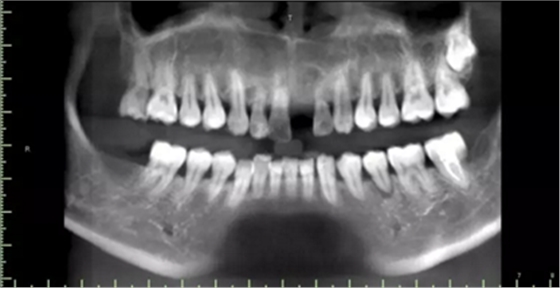

1.術(shù)前CT

2.術(shù)前植體設(shè)計(jì)